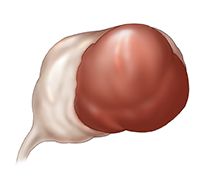

Endometrioma

Sometimes tissue similar to the lining of the uterus (endometrium) grows and becomes part of the ovary. This kind of cyst is often called a chocolate cyst because of its dark brown color. These cysts can grow on one or both ovaries. They often cause pain, especially around menstruation or during sex.